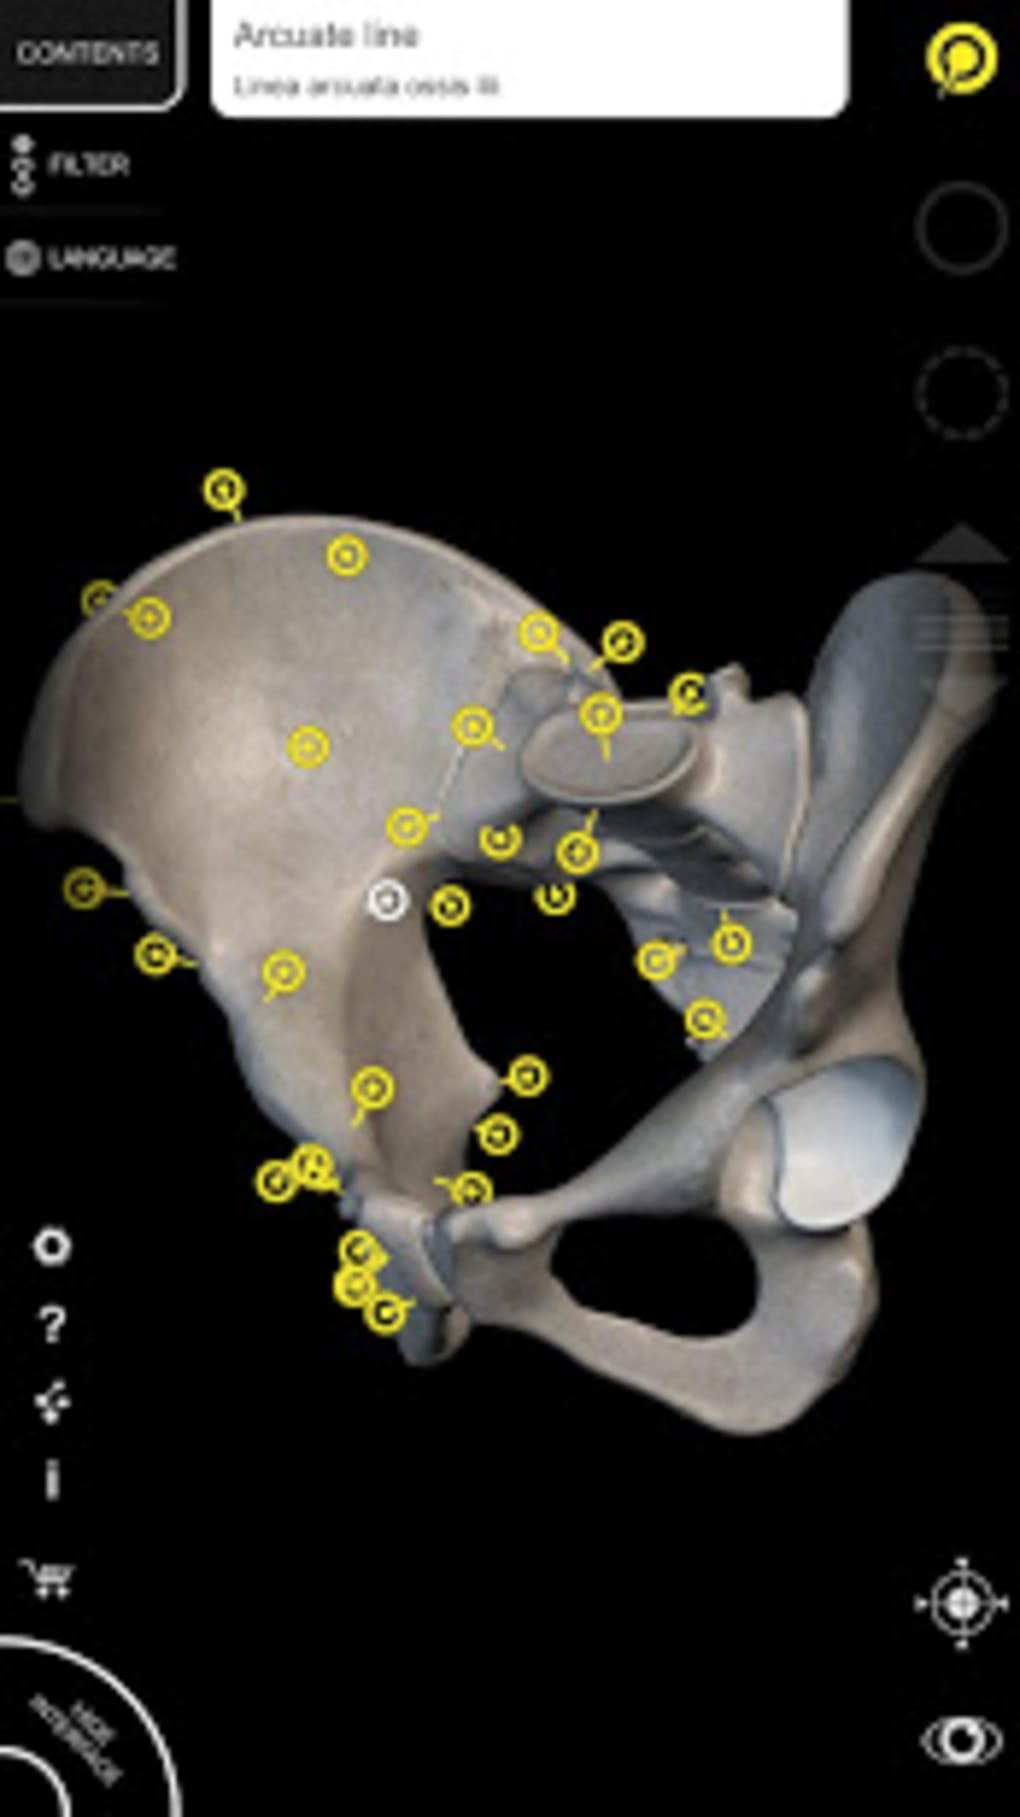

The app is based on the 3D model of the human body which is built with skeleton, muscles, bones, organs, and tissues. The anatomical models you will see in this app are the Respiratory System, Lymphatic system, Digestive System, Cardiovascular system, Eye and ear, and more.This app allows you to view the anatomy from a variety of angles, which makes it easy to study and understand.